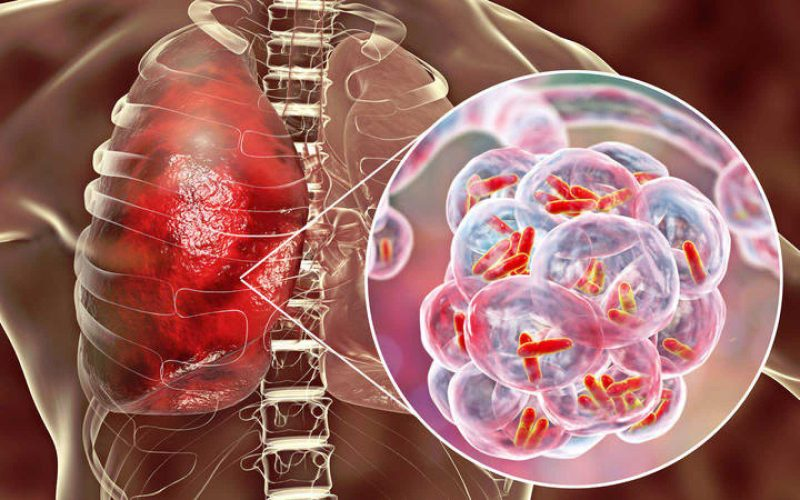

కోవిడ్ మహమ్మారి ప్రభావం, అనేక కేసులు నిర్ధారణ కాకపోవడం, చికిత్సను పూర్తిగా చేయకపోవడం, మొండి క్షయంగా మారడం, సరైన అవగాహన లేకపోవడం—ఇలాంటి అనేక కారణాల వల్ల క్షయ నిర్మూలన ఇంకా దూరంగానే ఉంది. ఇవి కాకుండా, ‘నిద్రాణ క్షయ’ (Latent TB) కూడా పెద్ద సవాలుగా మారింది. ఇది నిజంగా నిశ్శబ్ద బాంబులాంటిది. ఎప్పుడైనా యాక్టివ్ క్షయగా మారే ప్రమాదం ఉంది.

నిద్రాణ క్షయలో ఎలాంటి లక్షణాలు కనిపించవు. ఎక్స్రేలో కూడా స్పష్టంగా గుర్తించడం కష్టం. కళ్లె పరీక్షల్లోనూ బయటపడదు. ముఖ్యంగా, ఈ దశలో ఉన్నవారి నుంచి ఇతరులకు వ్యాధి వ్యాపించదు. అందువల్ల చాలామంది దీన్ని తేలికగా తీసుకుంటారు. కానీ ఇక్కడే పెద్ద పొరపాటు జరుగుతోంది.

రోగనిరోధక శక్తి తగ్గినప్పుడు, నిద్రాణ క్షయ ఎప్పుడైనా యాక్టివ్ క్షయగా మారే ప్రమాదం ఉంది. సాధారణంగా, బలమైన రోగనిరోధక శక్తి ఉన్నవారిలో జీవితకాలంలో 5–10 శాతం మాత్రమే ఇది యాక్టివ్ క్షయగా మారుతుంది. కానీ క్షయ బాధితులతో సన్నిహితంగా ఉంటే ఈ ముప్పు 15–21 రెట్లు పెరుగుతుంది.